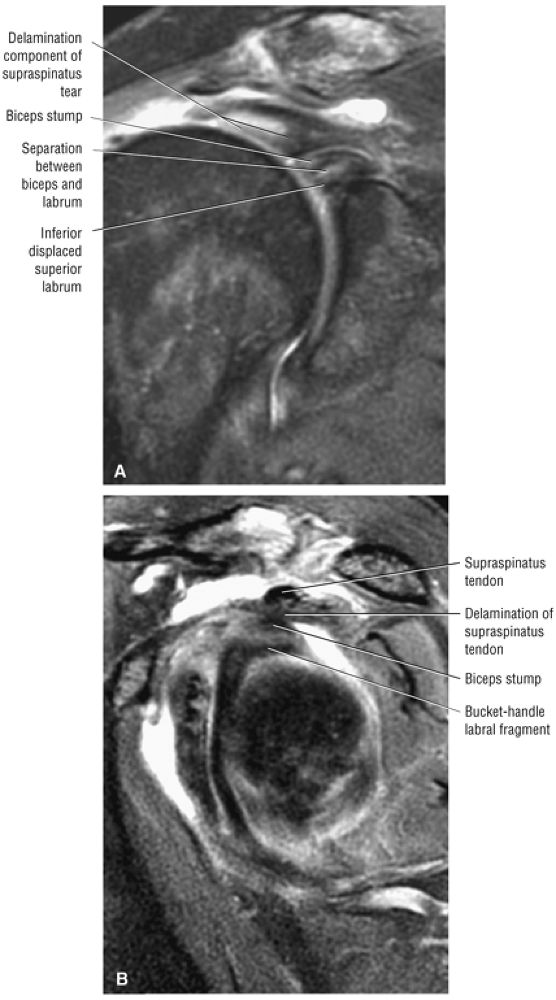

FIGURE 8.102 ● (A) The anterior undersurface of the acromion and the coracoacromial ligament form the coracoacromial arch. The subacromial subdeltoid bursa facilitates the passage of the rotator cuff and proximal humerus under the coracoacromial arch. (B) A superior axial image shows the anterior-to-posterior extent of the coracoacromial (CA) ligament perpendicular to the supraspinatus tendon. The fluid in the subacromial-subdeltoid bursa represents fluid between two serosal surfaces in contact with each other. One serosal surface is contributed by the undersurface of the coracoacromial arch and deltoid, and the other serosal surface is on the bursal side of the cuff.

|

![]() |

FIGURE 8.103 ● Pseudospur. The normal broad attachment of the coracoacromial ligament to the inferior surface of the acromion is shown on (A) T1-weighted coronal oblique and (B) sagittal oblique images. The low-signal-intensity acromial cortex (black arrows) and adjacent coracoacromial ligament and lateral slip of the deltoid attachment (white arrows) give the false impression of a small subacromial spur in the coronal plane. This pseudospur should not be misinterpreted as impingement; otherwise, unnecessary acromioplasties may be performed on patients with a normal coracoacromial ligament attachment and no associated acromial spurs.